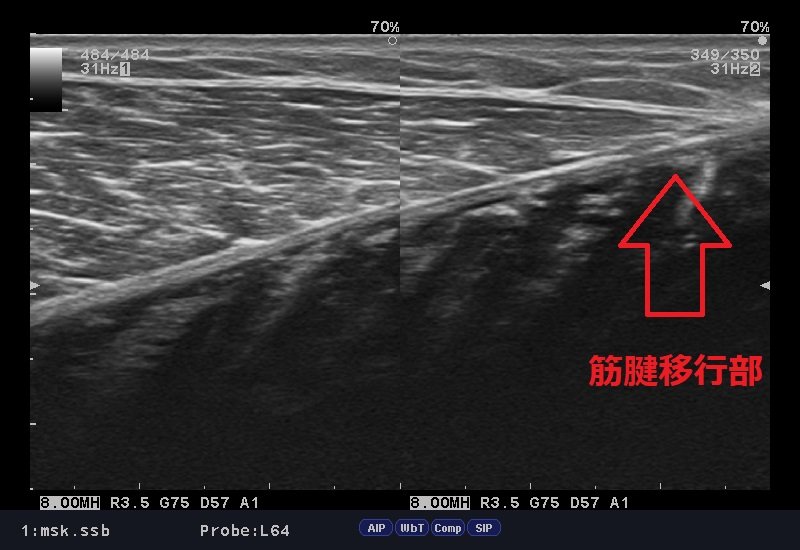

下のエコー画像、ふくらはぎの筋腹内にも腫れが残っていますが、筋腱移行部ラインが不明瞭となっております。

これは肉離れの兆候となっており、まだ組織が修復されていないサインでもあります。

エコー検査は筋肉の状態を正確に確認でき、的確に治療をできます。